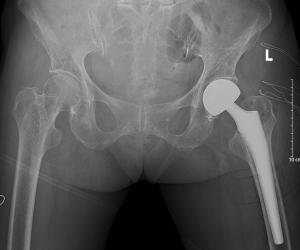

济南南郊医院骨一科成功为93岁高龄老人实施股骨头置换术

济南南郊医院骨一科手术团队成功为矽肺患者实施全髋关节置换术

南郊医院骨一科成功为右股骨颈骨折患者实施“人工股骨头置换术”